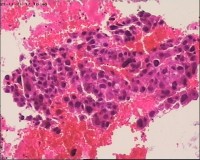

性别

女

年龄

20岁

停经3月,阴道不规则流血7天。

宫刮物

灰白灰红碎组织一堆,大小为7*6*1cm,部分组织呈水泡状

水肿的绒毛和蜕膜,没看到增生的滋养细胞。必要时可做IHC除外部分葡萄胎,并结合临床HCG。

雾蒙蒙:

需要除外一下部分性水泡状胎块可能

考虑葡萄胎